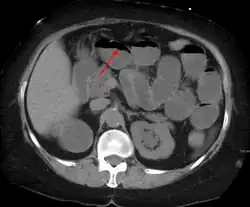

Causes of bowel obstruction include adhesions, hernias, volvulus, endometriosis, inflammatory bowel disease, appendicitis, tumors, diverticulitis, ischemic bowel, tuberculosis and intussusception.[1][2] Small bowel obstructions are most often due to adhesions and hernias while large bowel obstructions are most often due to tumors and volvulus.[1][2] The diagnosis may be made on plain X-rays; however, CT scan is more accurate.[1] Ultrasound or MRI may help in the diagnosis of children or pregnant women.[1]

The main diagnostic tools are blood tests, X-rays of the abdomen, CT scanning, and ultrasound. If a mass is identified, biopsy may determine the nature of the mass.

Radiological signs of bowel obstruction include bowel distension (small bowel loops dilated >3 cm) and the presence of multiple (more than 2) air-fluid levels on supine and erect abdominal radiographs.[16] Ultrasounds may be as useful as CT scanning to make the diagnosis.[17]

Contrast enema or small bowel series or CT scan can be used to define the level of obstruction, whether the obstruction is partial or complete, and to help define the cause of the obstruction. The appearance of water-soluble contrast in the cecum on an abdominal radiograph within 24 hours of it being given by mouth predicts resolution of an adhesive small bowel obstruction with sensitivity of 97% and specificity of 96%.[18]